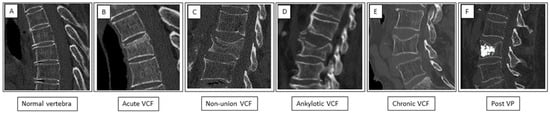

Figure 1. Patterns of vertebrae appearance on sagittal spine CT. (A) Normal vertebra—retained height and continuous cortex. (B) Acute VCF showing a “step defect” in the anterior border and a “zone of impaction” caused by impaction of the trabeculae. (C) Non-union fracture—a non-healed fracture with an intervertebral cleft (white arrow). (D) Ankylotic fracture—a transverse fracture below an ankylotic spine segment. (E) Chronic fracture showing loss of height and smooth cortical borders. (F) State after percutaneous vertebroplasty (Post VP)—chronic fracture with loss of height and hyperdense cement in the vertebral body.

A description of the CT pattern was documented for each vertebra according to the following (Figure 1): (A) normal vertebra (no fracture); (B) acute VCF displaying CT signs of loss of height or anterior wedge deformity with endplate irregularity, cortical incontinuity, step defects, increased density zone of impaction, and soft-tissue edema or hematoma surrounding the vertebral body; (C) non-union of a VCF displaying a non-healed fracture with an intravertebral cleft, also known as Kümmell’s disease; (D) ankylotic VCF displaying a transverse fracture below an ankylotic spine segment; (E) chronic VCF displaying loss of height or anterior wedge deformity with smooth cortical borders; and (F) following percutaneous vertebroplasty (Post VP) displaying cement within the vertebral body.